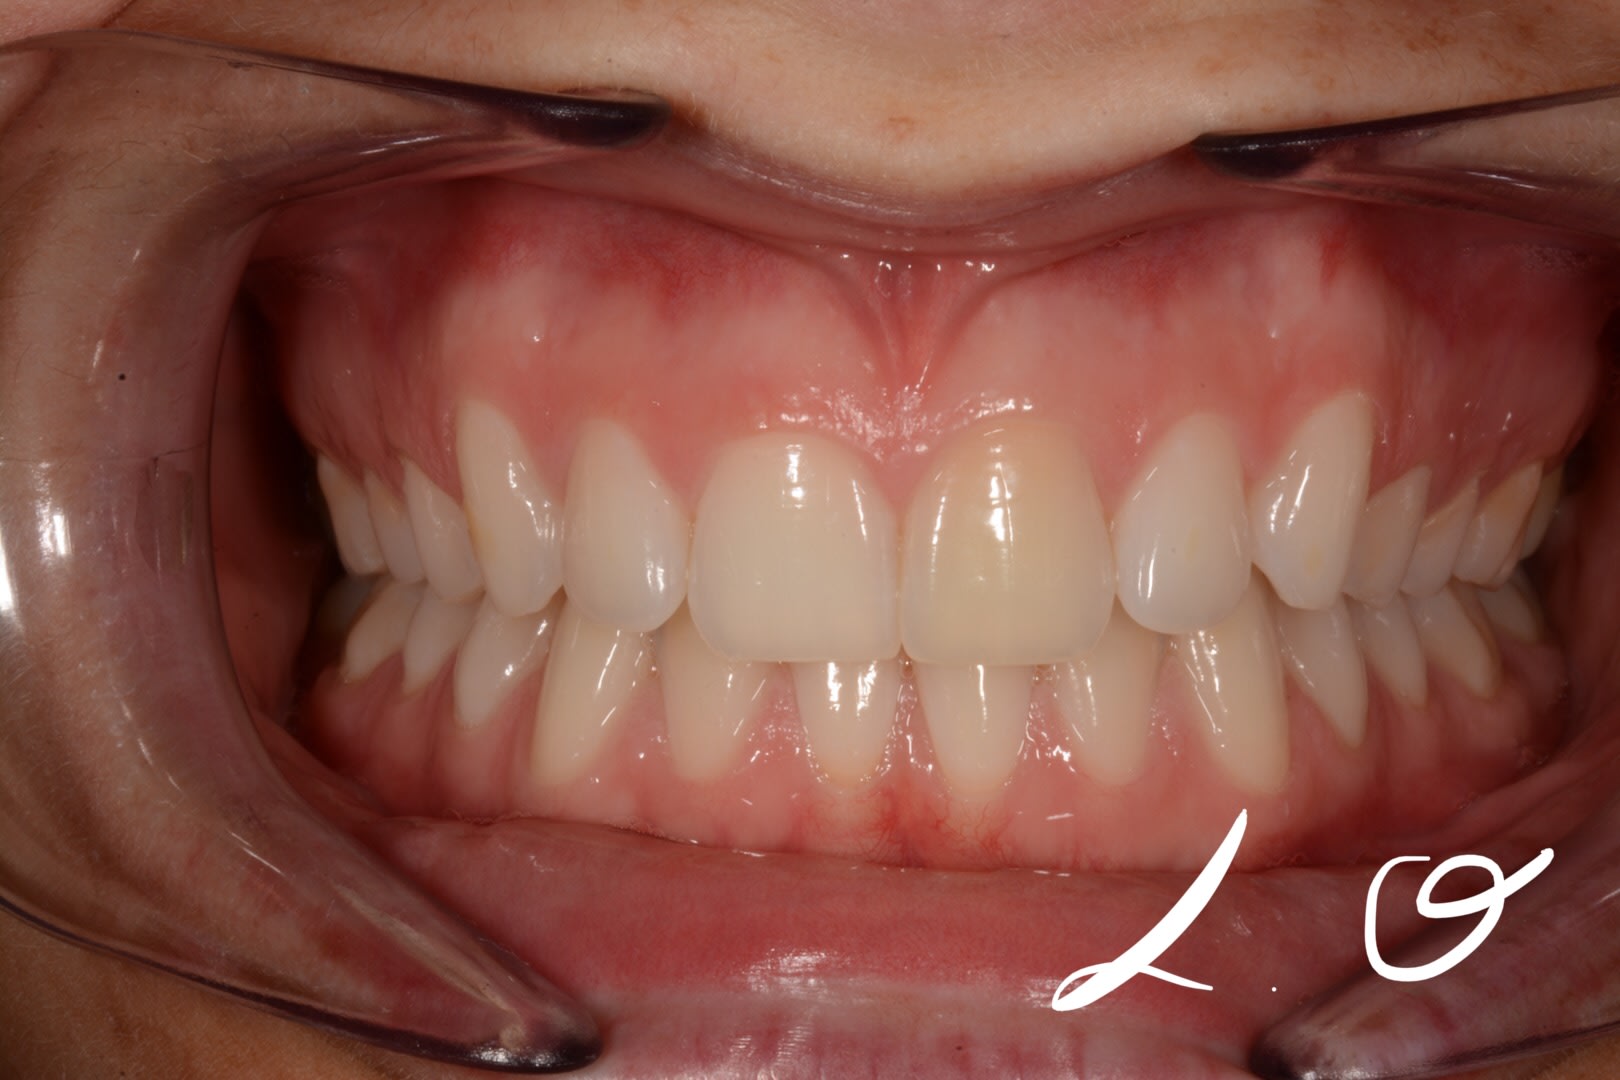

Une de mes amie âgée de 25 ans s'inquiète de voir sa dent 21 changer de couleur et me demande mon avis. Elle ne présente pas de souci de santé et ne fume pas.

Le changement de couleur de la dent s'est initié il y a un an environ et s'accentue selon ses dires.

Forcément je lui ai demandé si elle avait reçu un choc mais strictement rien.

A l'examen : pas de douleur à la percussion, pas de douleur à la palpation vestibulaire. Le test au froid est positif non douloureux, mais quand meme plus difficile (long) à obtenir que sur la 11.

N'est ce pas juste une usure plus importante de l'émail sur la 21, due à une position plus vestibulée? (elle me parait légèrement en rotation et en position plus vestibulée que la 11)

Après, la patiente a aussi pu insister plus sur cette dent au niveau du brossage (voir a peut-être utilisé des produits pour blanchir la dent) pour atténuer le "jaunissement", mais n'a fait qu'aggraver le cas en faisant plus ressortir la tonalité de sa dentine...